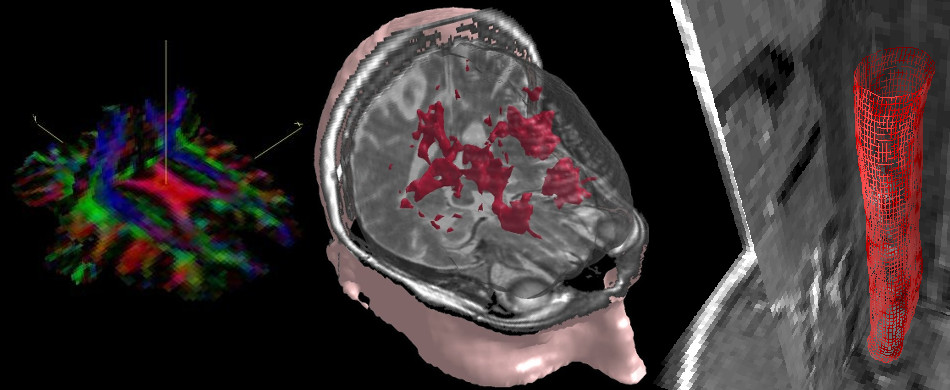

| 9.DWI(拡散画像)の解析 | 拡散テンソル画像とファイバー・トラッキング | ![]() |

| 7.フォローアップ | 経時的な局所脳病変の解析 | ![]() |

| 脳と脊髄:脳体積と萎縮の計測 | ![]() |

| 6.領域分割 | マスキングとあいまい領域の分割 | ![]() |